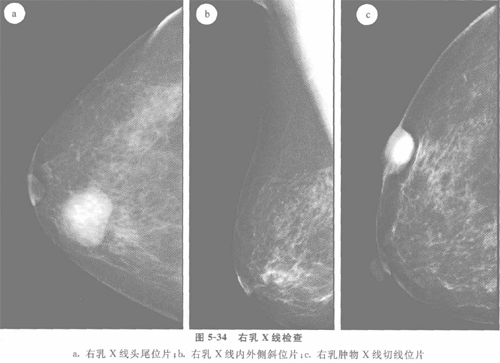

乳腺纤维瘤X光

乳腺纤维腺瘤的肿块好发于乳房的外上象限。腺瘤常为单发,亦有多发者。腺瘤呈圆形或卵圆形,直径以1~3cm者较为多见,亦有更小或更大者,偶可见巨大者。表面光滑,质地坚韧,边界清楚,与皮肤和周围组织无粘连,活动度大,触之有滑动感。腋下淋巴结无肿大。腺瘤多无痛感,亦无触痛。其大小性状一般不随月经周期而变化。肿块通常生长缓慢,可以数年无变化,但在妊娠哺乳期可迅速增大,个别的可于此时发生肉瘤变。